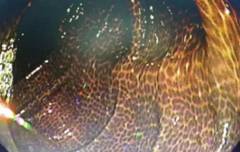

肠镜可见,其结肠已大范围发黑,黑色素呈条纹状、斑片状沉着在结肠黏膜上,仿佛"豹纹",又像蛇皮,被确诊为结肠黑变病。见下图:

结肠黑变病(MC)是结肠黏膜固有层中巨噬细胞内色素聚集的一种黏膜色素沉着性为特征的非炎性、良性可逆性病变,常与息肉、肿瘤伴发,也有观点认为有一定的癌变几率。